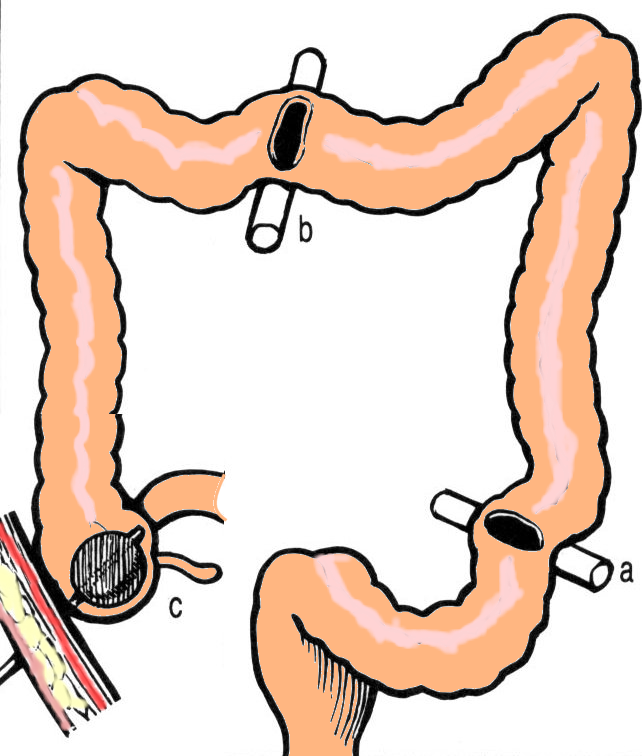

COLONOSTOMII - CECOSTOMIA, COLOSTOMIA ILIACA STANGA

COLONOSTOMII - CECOSTOMIA, COLOSTOMIA ILIACA STANGA Colostomia este actul chirurgical prin care se realizeaza derivatia catre exterior a continutului colic. Consta in aducerea la piele a colonului, in amonte de o leziune tumorala. Aceste iCiteste tot ... 5652 cuvinte

Dimensiune mare

+ cu imagini |